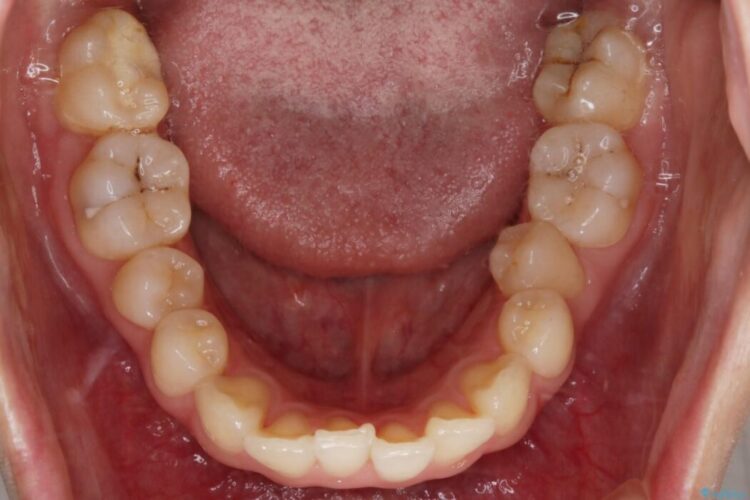

【20代女性】ブライダルに向けた矯正できれいなスマイルラインへ

笑った時に見える歯並びをきれいにしたいとの主訴で来院されました。

ガタつきの度合いから抜歯は不要と判断しましたので、マイクロインプラントを用いて歯全体を遠心移動させていくことでねじれや噛み合わせのズレを改善していく計画を立てました。